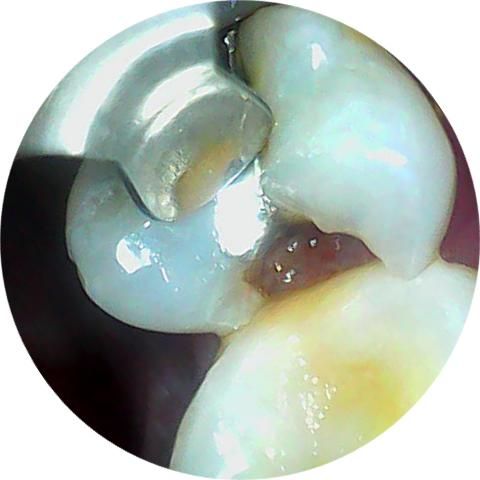

깨진 치아 지금이라도 치료 받아야되나여

며칠 아프다가 안 아파져서 잊고 살았는데, 어떤 상태인지 궁금해서 카메라로 찍어봤더니 요래 됐네요;;

1년 쯤 된 것 같은데 지금이라도 가야하나요?

• 1번 째 사진

이전의 아말감이 떨어져 나가고 내부로 충치가 생긴것으로 보입니다. 해당부위에는 이물질이 끼게 되어 충치가 더 생길수 있으며 치아가 파절될수 있기때문에 빠른시일내에 치료를 해주는것이 좋습니다.